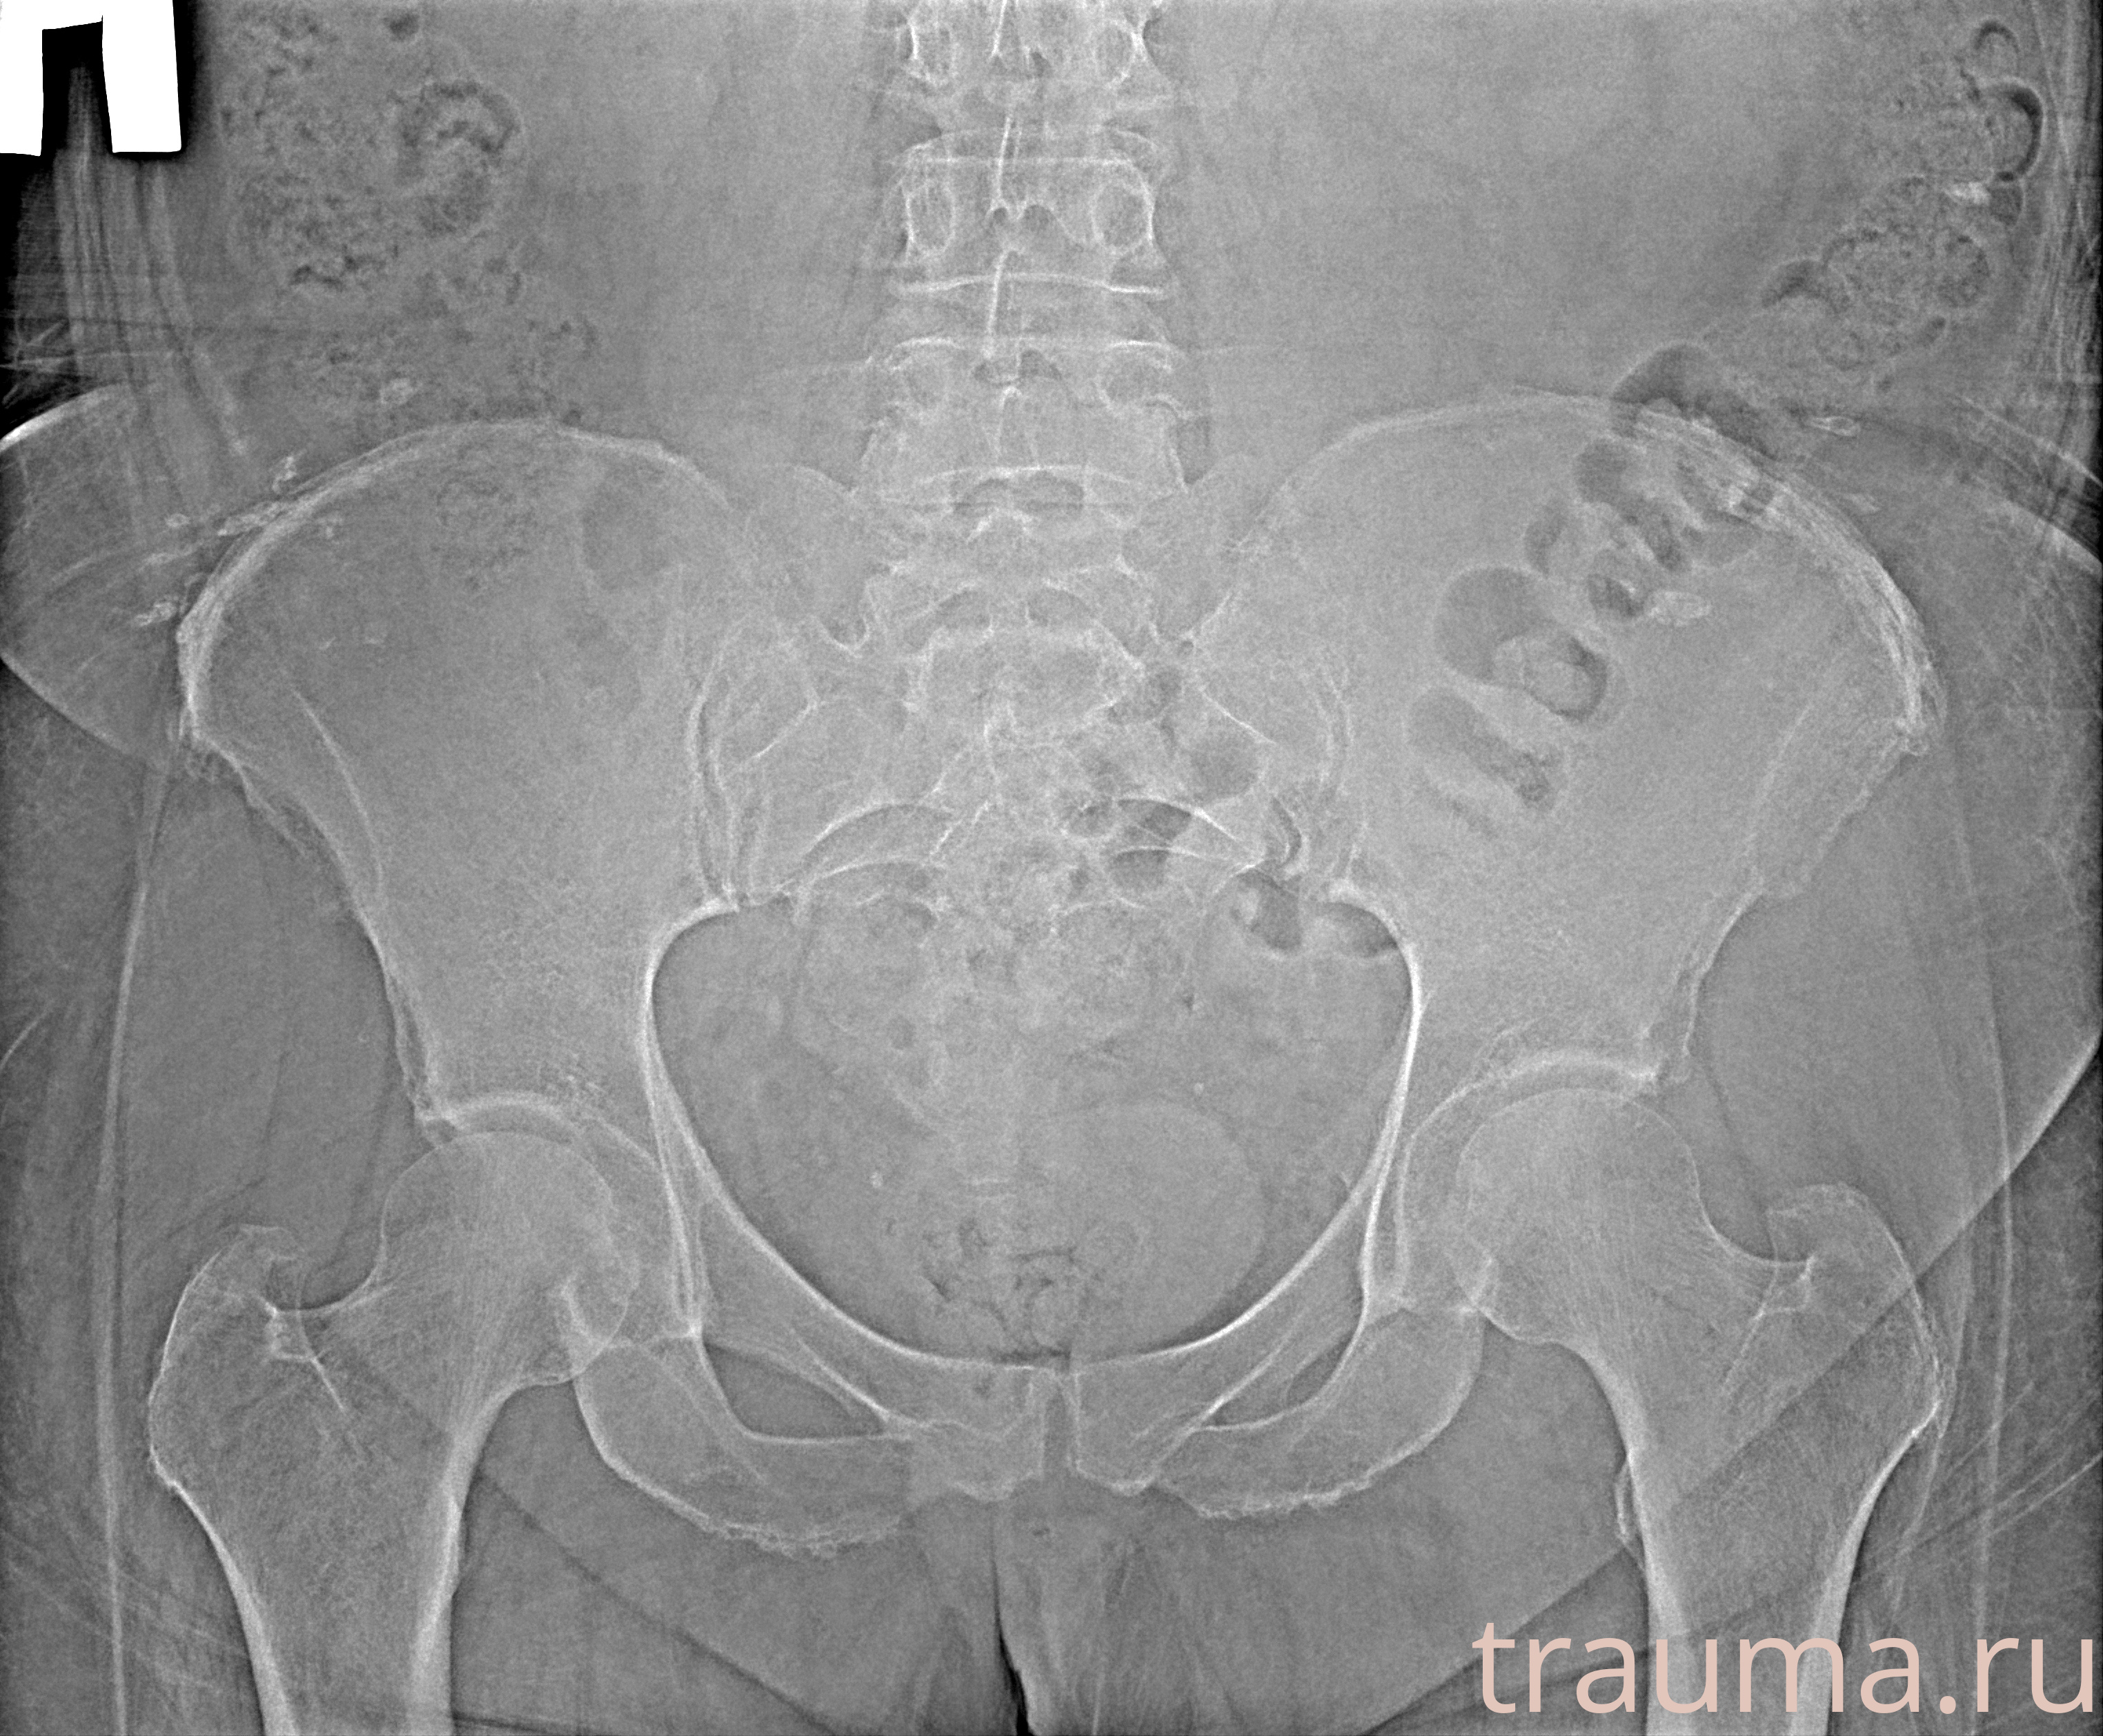

Рентген на дому: по вашему адресу приезжает врач-рентгенолог, травматолог-ортопед с мобильным рентгеновским аппаратом, проводит диагностику травмы или заболевания, делает необходимые рентгенограммы, дает рекомендации по дальнейшему лечению. Получить качественные снимки в домашних условиях возможно благодаря уникальной методике, разработанной МосРентген Центром для института  Склифосовского

при переломе шейки бедра и пневмонии от компании МосРентген Центр - партнера Института имени Склифосовского